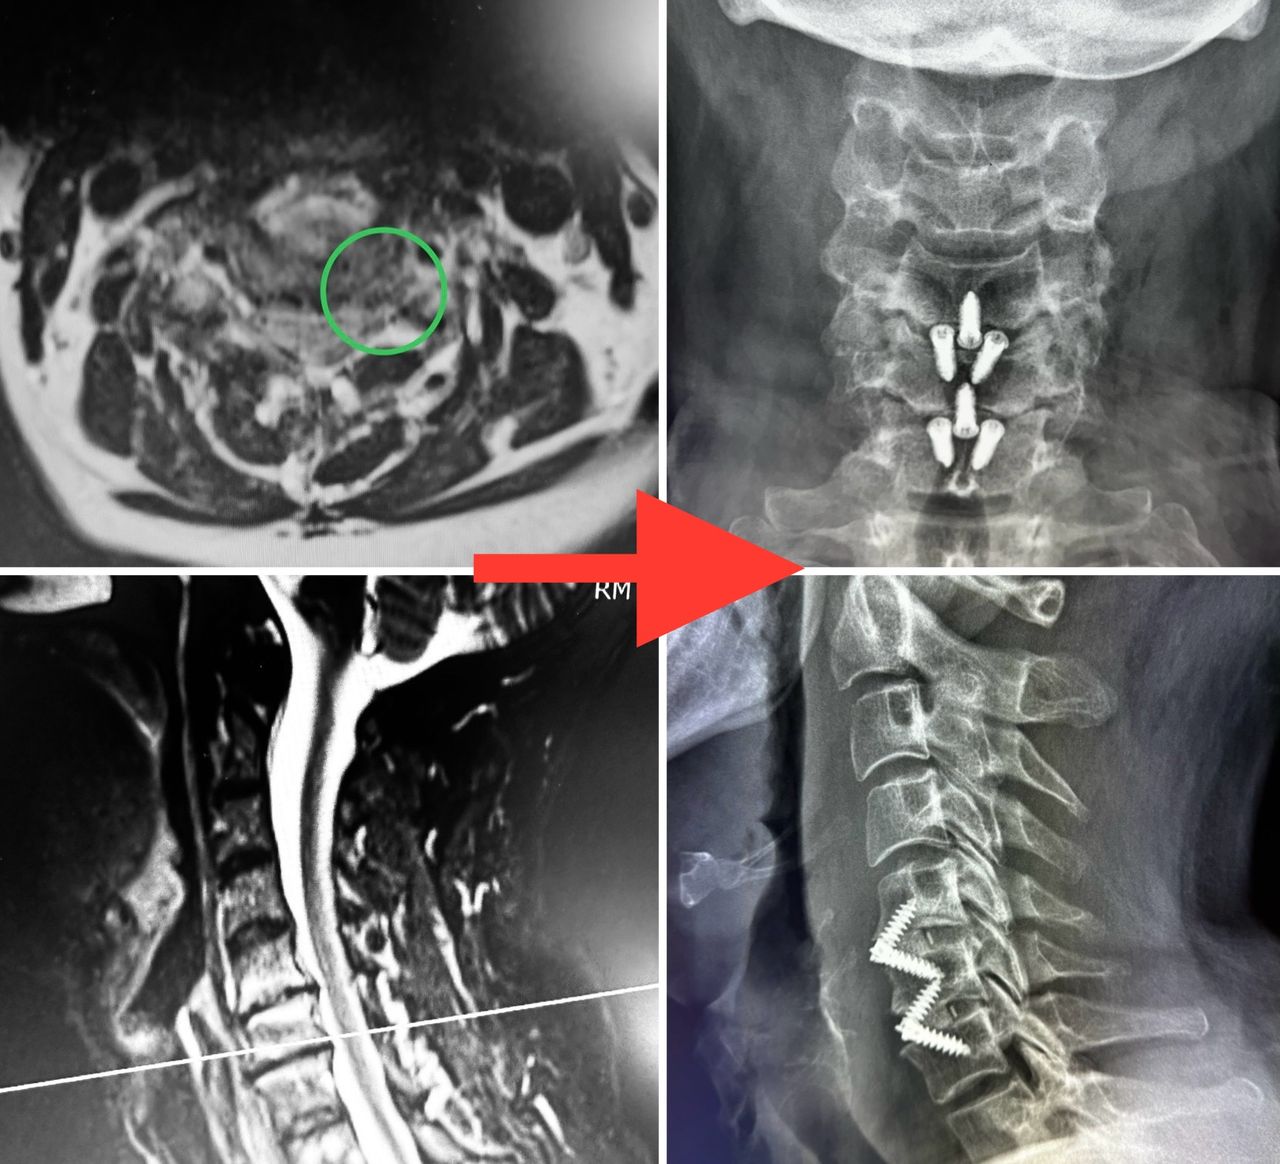

- Microchirurgia vertebrale

Microchirurgia dell’ernia cervicale e lombosacrale con con dimissione entro 24-48 ore

Microchirurgia stenosi del canale vertebrale, stenosi foraminali

- Chirurgia Mininvasiva percutanea vertebrale - stabilizzazioni e artrodesi intersomatiche (per fratture vertebrali, spondilolistesi, instabilità vertebrali, discopatie)

- Microchirurgia dei tumori spinali